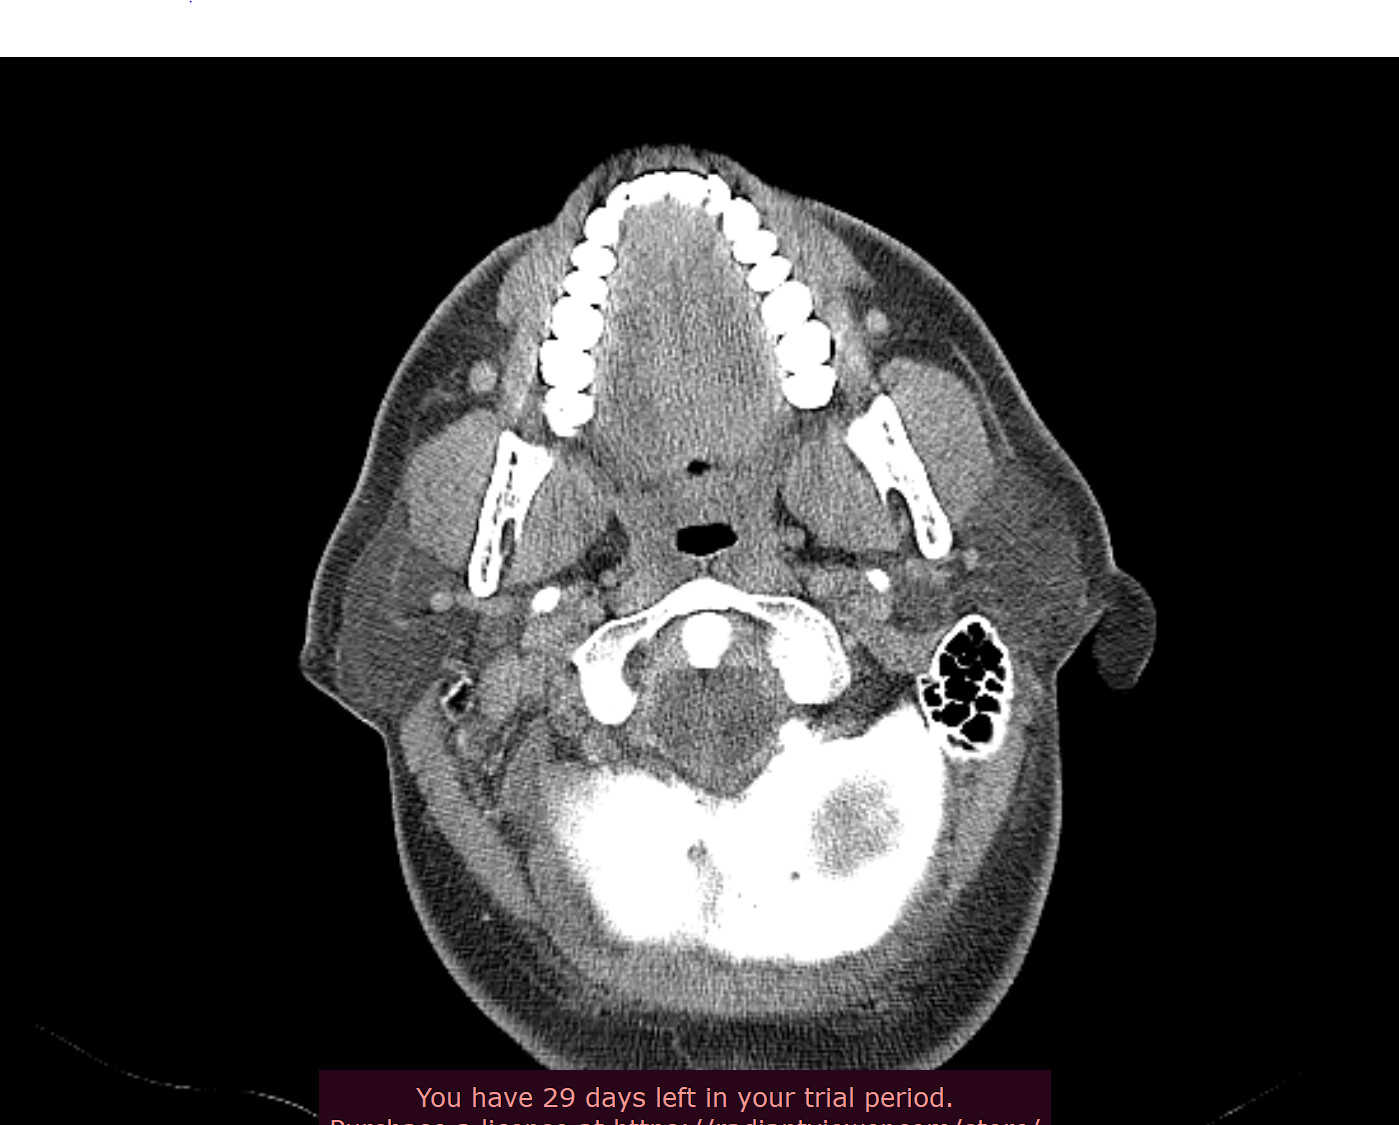

Hey all thanks, will take a look at the video shortly, in the meantime here’s the axial view, I think.

Thanks! I’m digging in a little more and have a few more shots.

Wow your right styloid/stylohyoid ligament is almost as long as it can get!! Your left side the styloid is around normal length and then there is a length of normal stylohyoid ligament, followed by a long pocket of calcified stylohyoid ligament.

yeah, it’s almost 6cm. Nakaji said symptoms sound like vascular, but as with all he sent me for a venogram. He also did mention the strange nature of my left styloid and how its arranged - bone, styloid, then calcified stylohyoid.

You have a crazy amount of calcification in your neck, @jalexy12. I hope Dr. Nakaji will help you! Did you by chance look into Dr. Cognetti, too, since he’s in your state?

Crazy styloids! It looks like on the 3D images that there’s a reasonable gap between the styloids & the C1 process, but sometimes it can be more obvious on the axial images, it could be that the digastric muscle is causing compression as @TML saw…